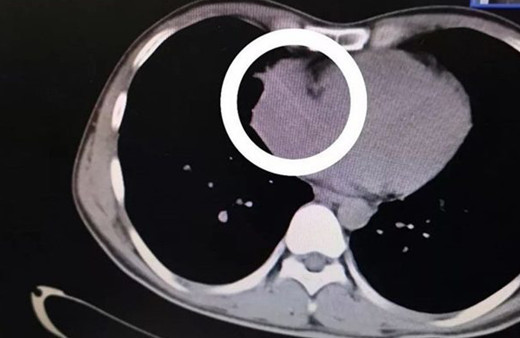

Kürdan